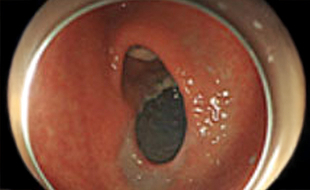

• 内視鏡的粘膜下層剥離術

早期胃癌と早期大腸癌の中には、開腹手術をすることなく切除できるものがあります。

• 内視鏡的粘膜切除術(胃や大腸のポリープを対象とした治療)

• 内視鏡的粘膜下層剥離術(主に早期の消化管癌を対象とした治療、胃、食道、大腸等)